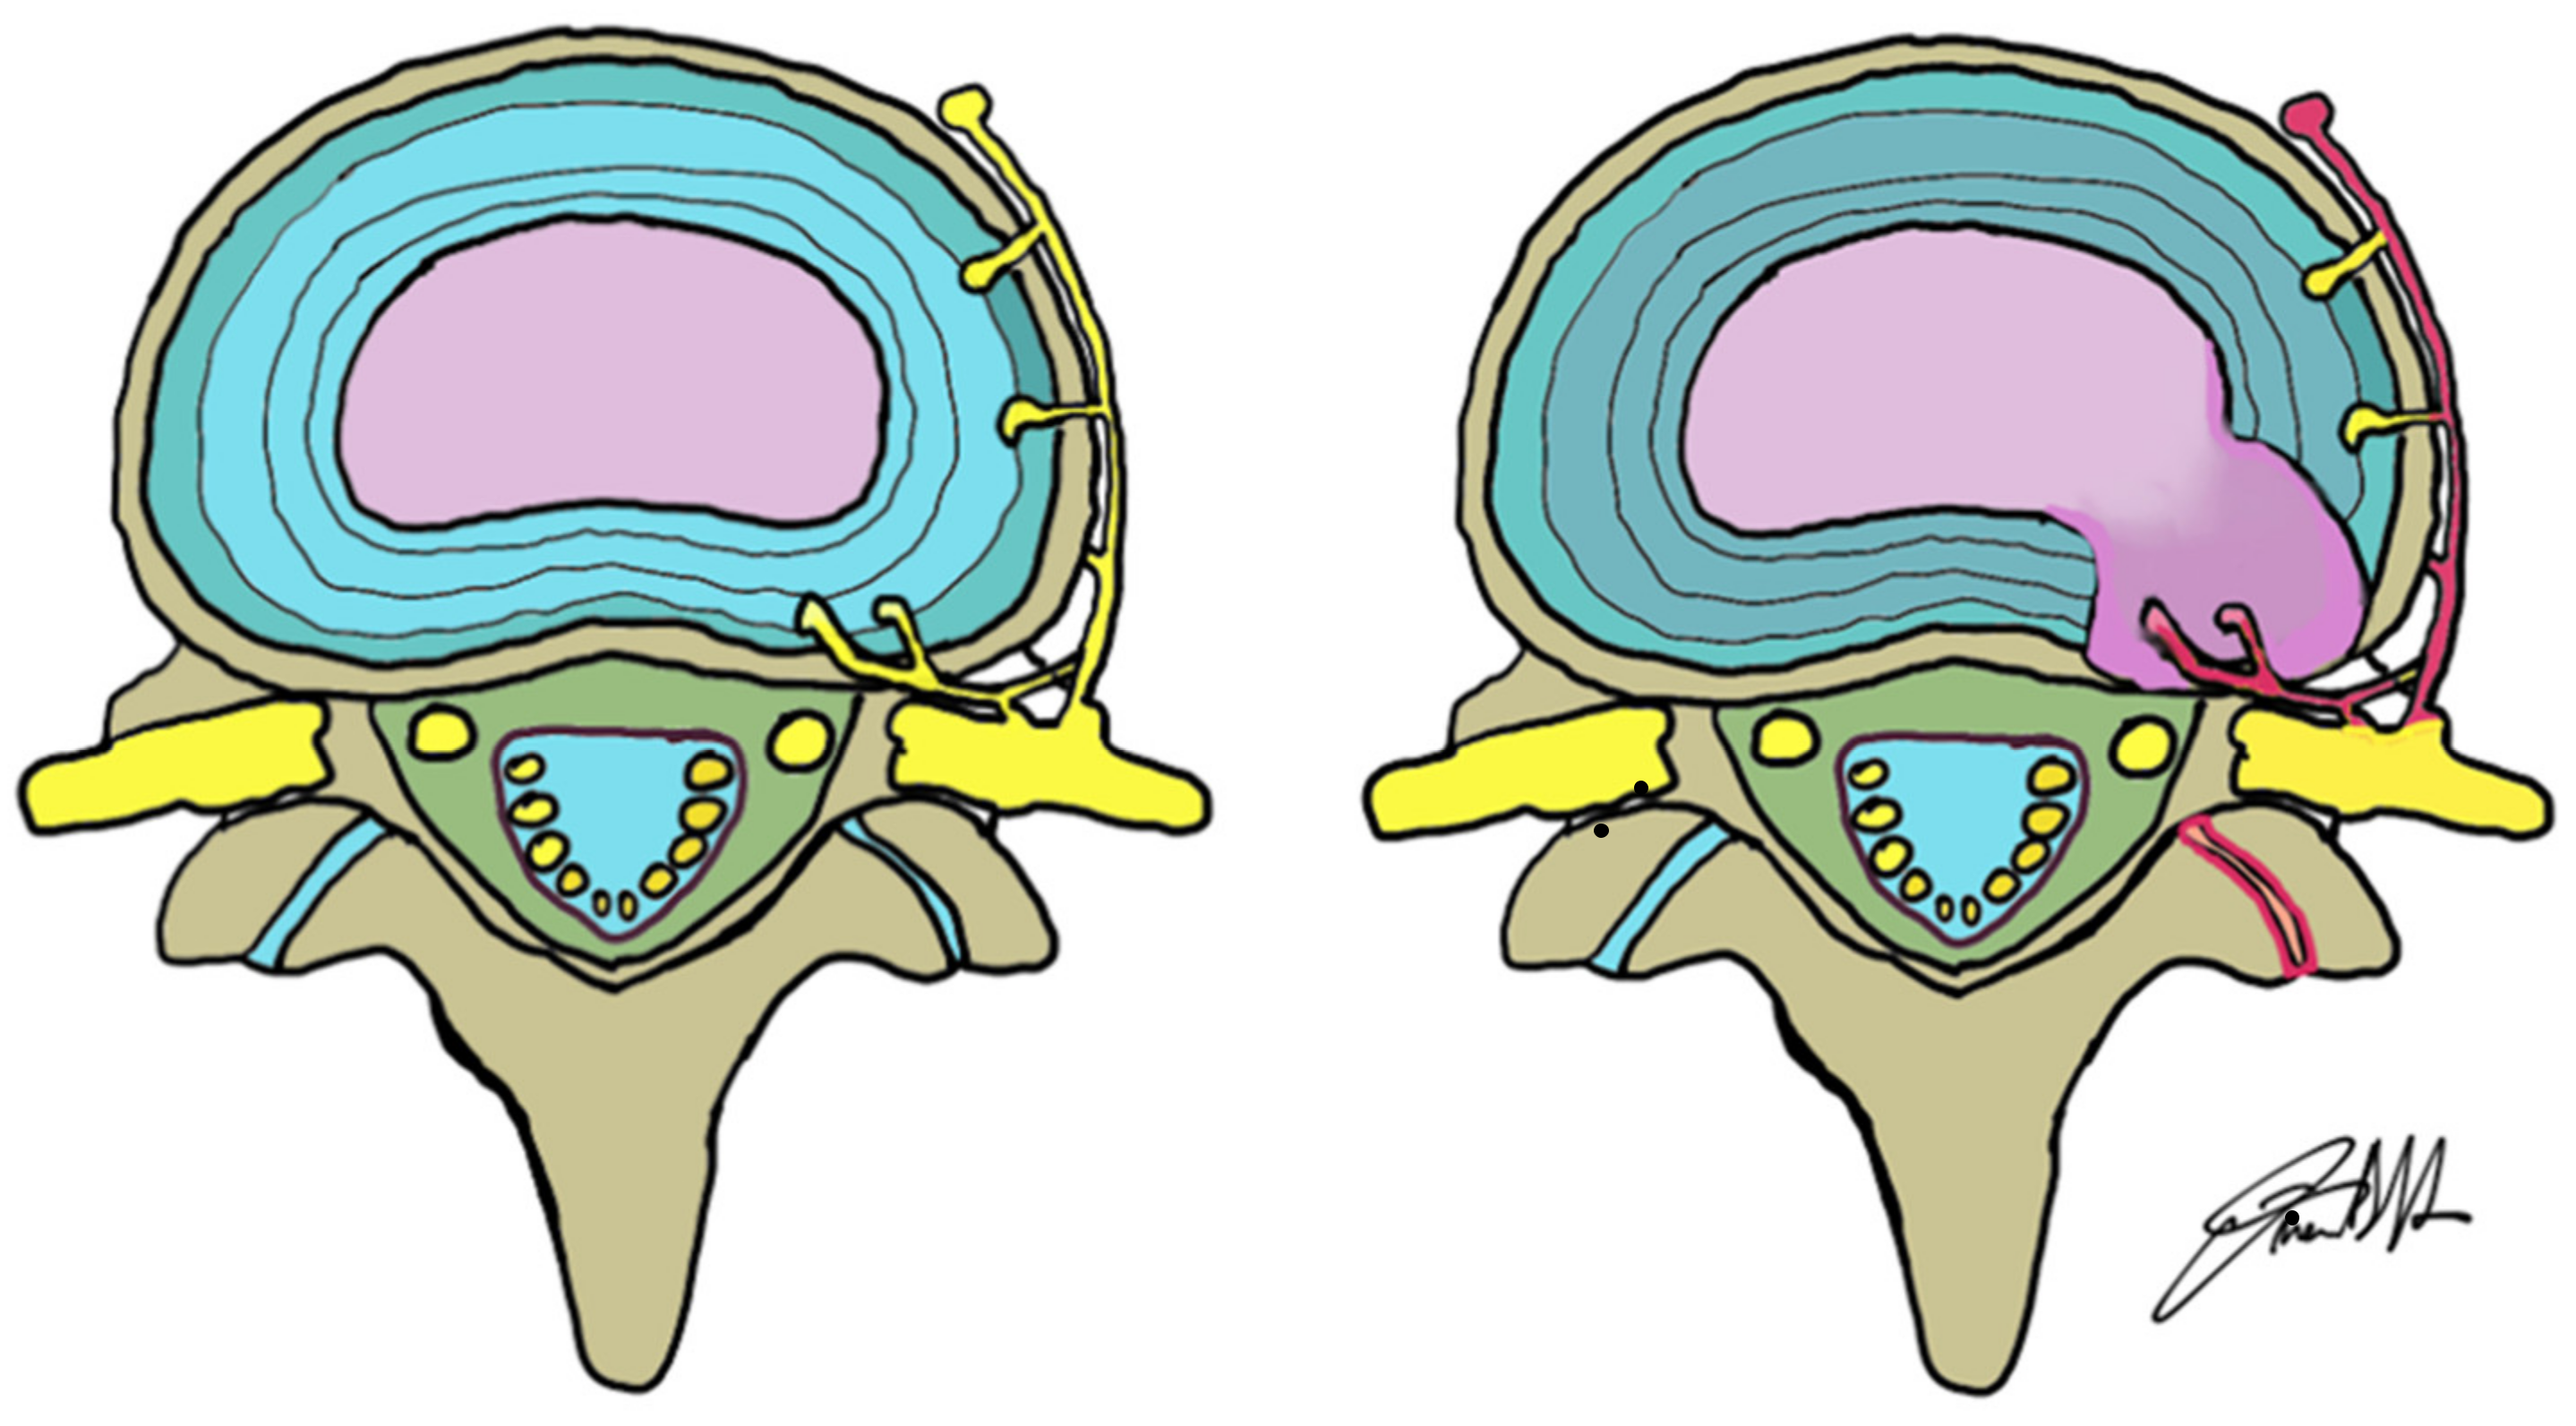

- Freemont, A.; Peacock, T.; Goupille, P.; Hoyland, J.; O’Brien, J.; Jayson, M. Nerve ingrowth into diseased intervertebral disc in chronic back pain. Lancet 1997, 350, 178–181. [Google Scholar] [CrossRef]

- Lama, P.; Le Maitre, C.L.; Harding, I.J.; Dolan, P.; Adams, M.A. Nerves and blood vessels in degenerated intervertebral discs are confined to physically disrupted tissue. J. Anat. 2018, 233, 86–97. [Google Scholar] [CrossRef] [Green Version]